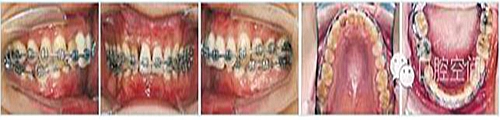

30歲男性患者,由于下前牙經(jīng)常咬傷上牙腭側(cè)牙齦,要求矯正調(diào)整咬合關(guān)系。上頜粘接直絲弓矯治器2個月后,下頜開始固定矯治,排齊牙列。4個月后下頜更換至0.018英寸鎳鈦絲,在下頜中切牙之間前庭溝處,局麻下切開黏膜,正中聯(lián)合部位植入一顆微螺釘(1.6 mm×9 mm,慈北醫(yī)療器械有限公司)。以直徑0.30 mm結(jié)扎絲連接微螺釘頭部,并穿出黏膜形成牽引鉤形狀。一周后開始加力,以微螺釘種植體支抗行閉合式牽引壓低下頜切牙。10個月后下切牙壓低良好,前牙覆頜正常,去除支抗螺釘。固定矯治20個月后,進入保持階段?;颊呙骖M像、X線片及頭影測量重疊圖見圖4,圖5,圖6,圖7,圖8,圖9,治療前后頭影測量結(jié)果見表2。

圖5病例1治療中像,以微螺釘支抗閉合式牽引開始壓低下切牙

圖6病例1治療中像,前牙覆正常